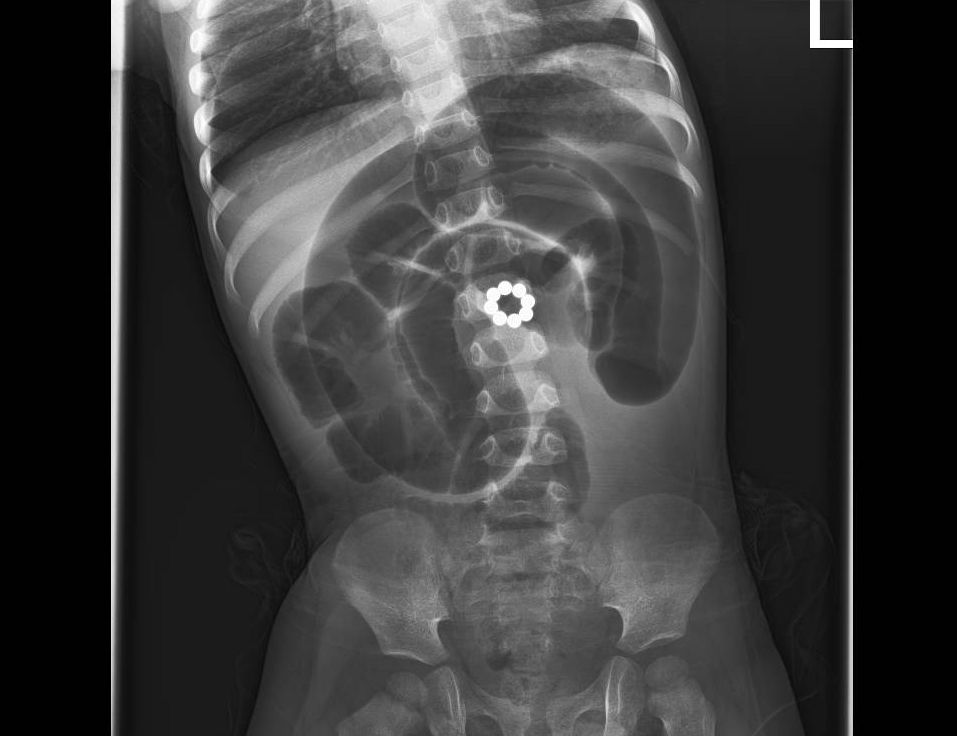

לדברי האב: "לאחר בדיקות מקיפות שכללו צילום חזה ובטן ואולטרסאונד גילו שהבן שלי בלע 8 מגנטים קטנים שגרמו לנזק רב במעיים. תוך שעה מרגע האבחון הוא כבר נכנס לניתוח חירום שהציל את חייו. הצוות שטיפל בנו עשה הכל ברגישות ומקצועיות, הם תמכו בנו ברגעים הקשים".

ד"ר מרק ארקוביץ', מנהל המחלקה לכירורגית ילדים, שניתח את הפעוט, מסביר: "מגנטים הם משחק מסוכן מאוד עבור ילדים. כאשר הפעוט בולע יותר ממגנט אחד, הם נצמדים זה לזה בתוך מערכת העיכול ועלולים לגרום לקרעים במעיים ואז תכולת המזון במעיים נפלטת אל הבטן וזו סכנת חיים של ממש. במקרה הזה המטופל הגיע עם נמק במעי אחרי ששמונה המגנטים שהוא בלע נצמדו אחד לשני וחסמו את זרימת הדם לאזור. המגנטים חסמו את תנועת המזון במערכת העיכול. בניתוח החירום הוצאנו את המגנטים, והסרנו שני אזורים שהיו נמקים וביצענו השקה של החלקים הבריאים. לצערי, פעוטות שבולעים מגנטים זה אירוע שכיח והטיפול הכי טוב הוא פשוט למנוע מקרים אלו. הרחיקו מהישג ידם של ילדים מגנטים ואם עולה חשש שהפעוט בלע מגנטים, או חפצים אחרים חשוב מייד לפנות לטיפול רפואי", סיכם ד"ר ארקוביץ'.